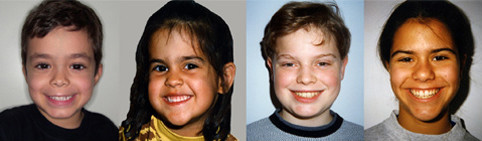

Φυσιολογικό Πρόσωπο και Φυσιολογικά Δόντια

Φυσιολογικό πρόσωπο είναι εκείνο που:

- έχει καλές αναλογίες

- είναι συμμετρικό ως προς την μέση γραμμή

- η άνω ή η κάτω γνάθος δεν προεξέχουν

- η κάτω γνάθος δεν αποκλίνει προς τα πλάγια

- τα χείλη βρίσκονται λίγο πίσω από μια νοητή γραμμή που ενώνει την κορυφή της μύτης με το πιγούνι

- το χαμόγελο αποκαλύπτει όσο το δυνατόν περισσότερα από τα πίσω δόντια ενώ τα επάνω πρόσθια δόντια δεν προεξέχουν από τα χείλη

- δεν παρατηρούνται έντονες συσπάσεις μυών